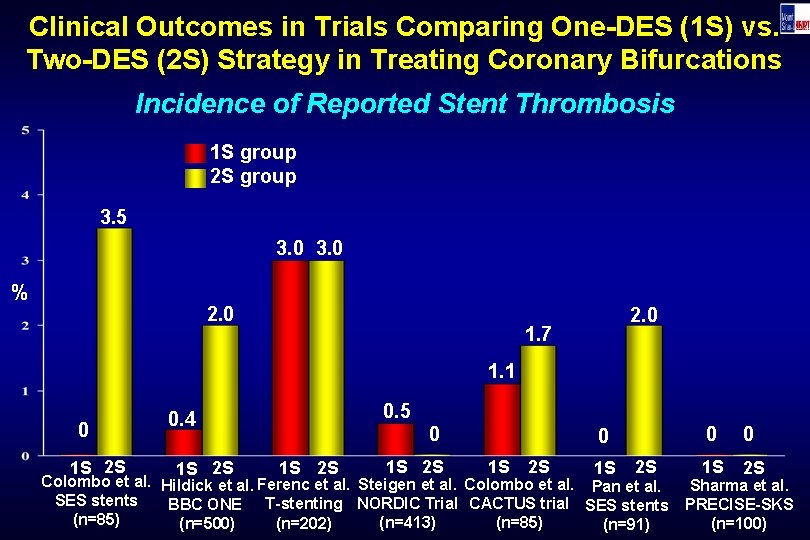

Clinical Outcomes in Trials Comparing One-DES (1 S) vs. Two-DES (2 S) Strategy in Treating Coronary Bifurcations Incidence of Reported Stent Thrombosis 1 S group 2 S group 3. 5 3. 0 % 2. 0 1. 7 1. 1 0 1 S 2 S 0. 5 0. 4 1 S 2 S 0 1 S 2 S Colombo et al. Hildick et al. Ferenc et al. Steigen et al. Colombo et al. Pan et al. SES stents BBC ONE T-stenting NORDIC Trial CACTUS trial SES stents (n=85) (n=413) (n=85) (n=202) (n=500) (n=91) 0 0 1 S 2 S Sharma et al. PRECISE-SKS (n=100)